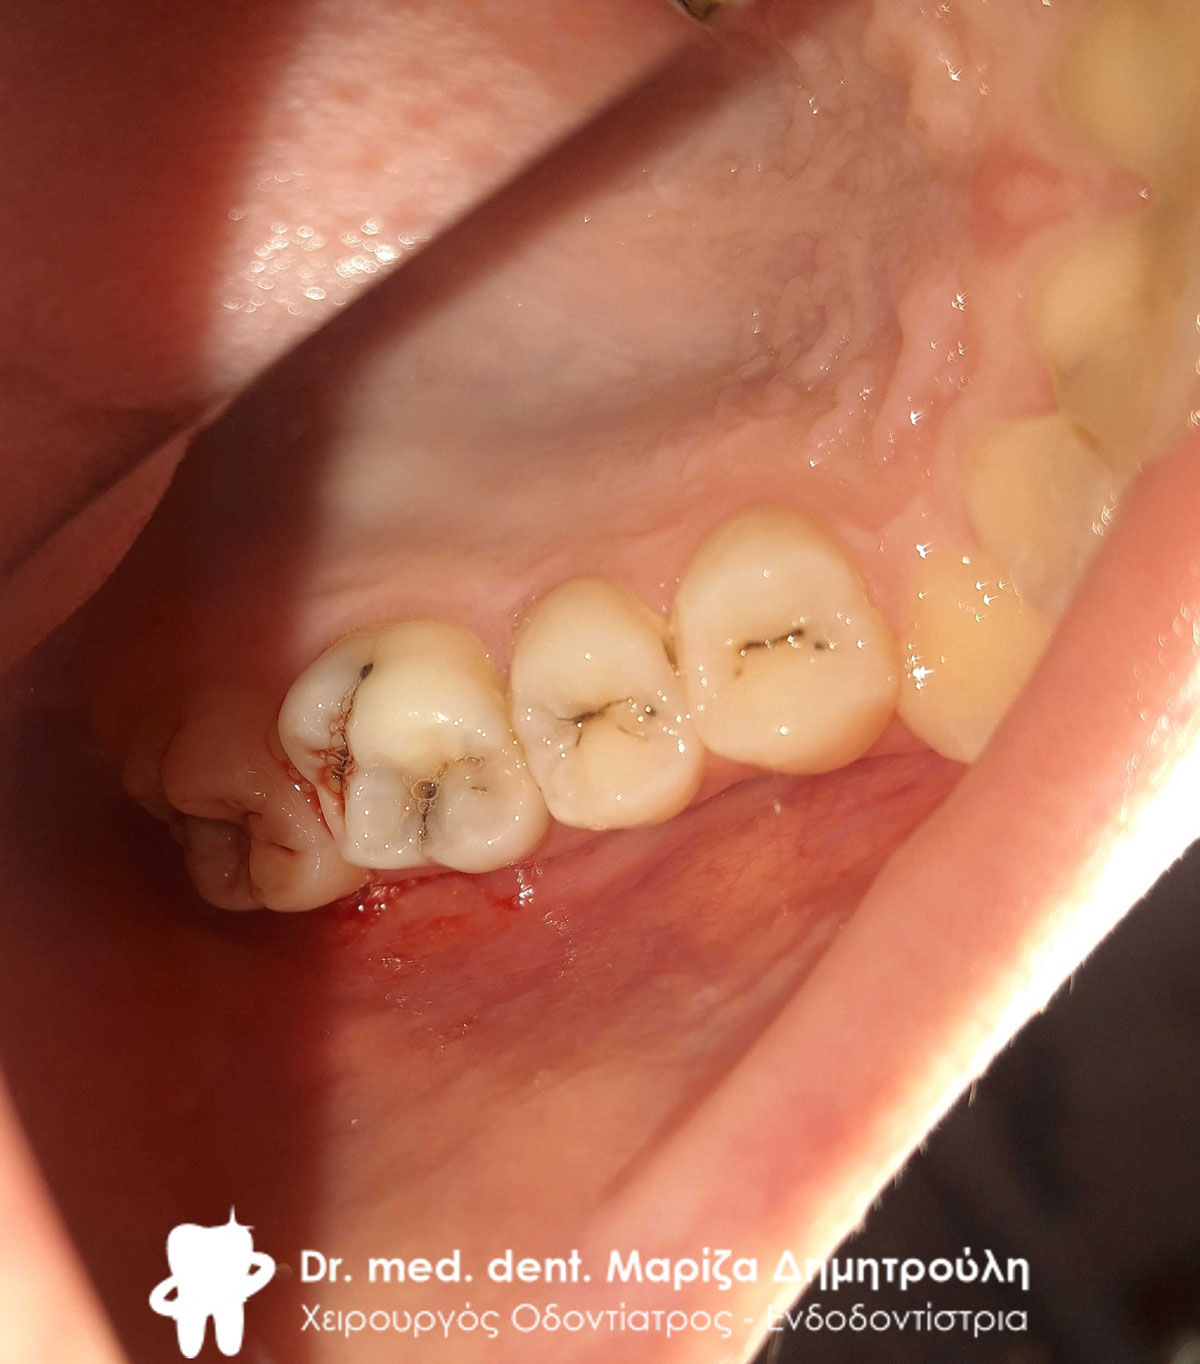

Αρχική κλινική εικόνα της αριστερής πλευράς της άνω γνάθου